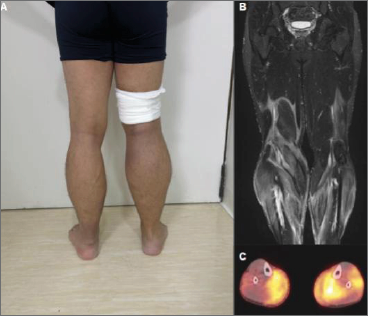

Initial laboratory screening was largely non-contributory, showing normal creatine kinase (CK) levels and a negative autoantibody panel. Magnetic resonance imaging (MRI) of the lower extremities revealed diffuse myositis involving the muscle, fascia, and subcutaneous tissue. A subsequent Fluorodeoxyglucose F-18 Positron Emission Tomography-Computed Tomography scan showed increased metabolic uptake in these affected areas, with a maximum Standardized Uptake Value (SUVmax) of 6.93.

Figure 1. A) Diffuse pseudohypertrophy of lower extremities. B) Magnetic Resonance (STIR, coronal view) showing marked inflammation of muscle, fascia and subcutaneous tissue. C PET-CT (fusion, axial view) of lower extremities demonstrating diffuse hypermetabolism of muscle and fascia.